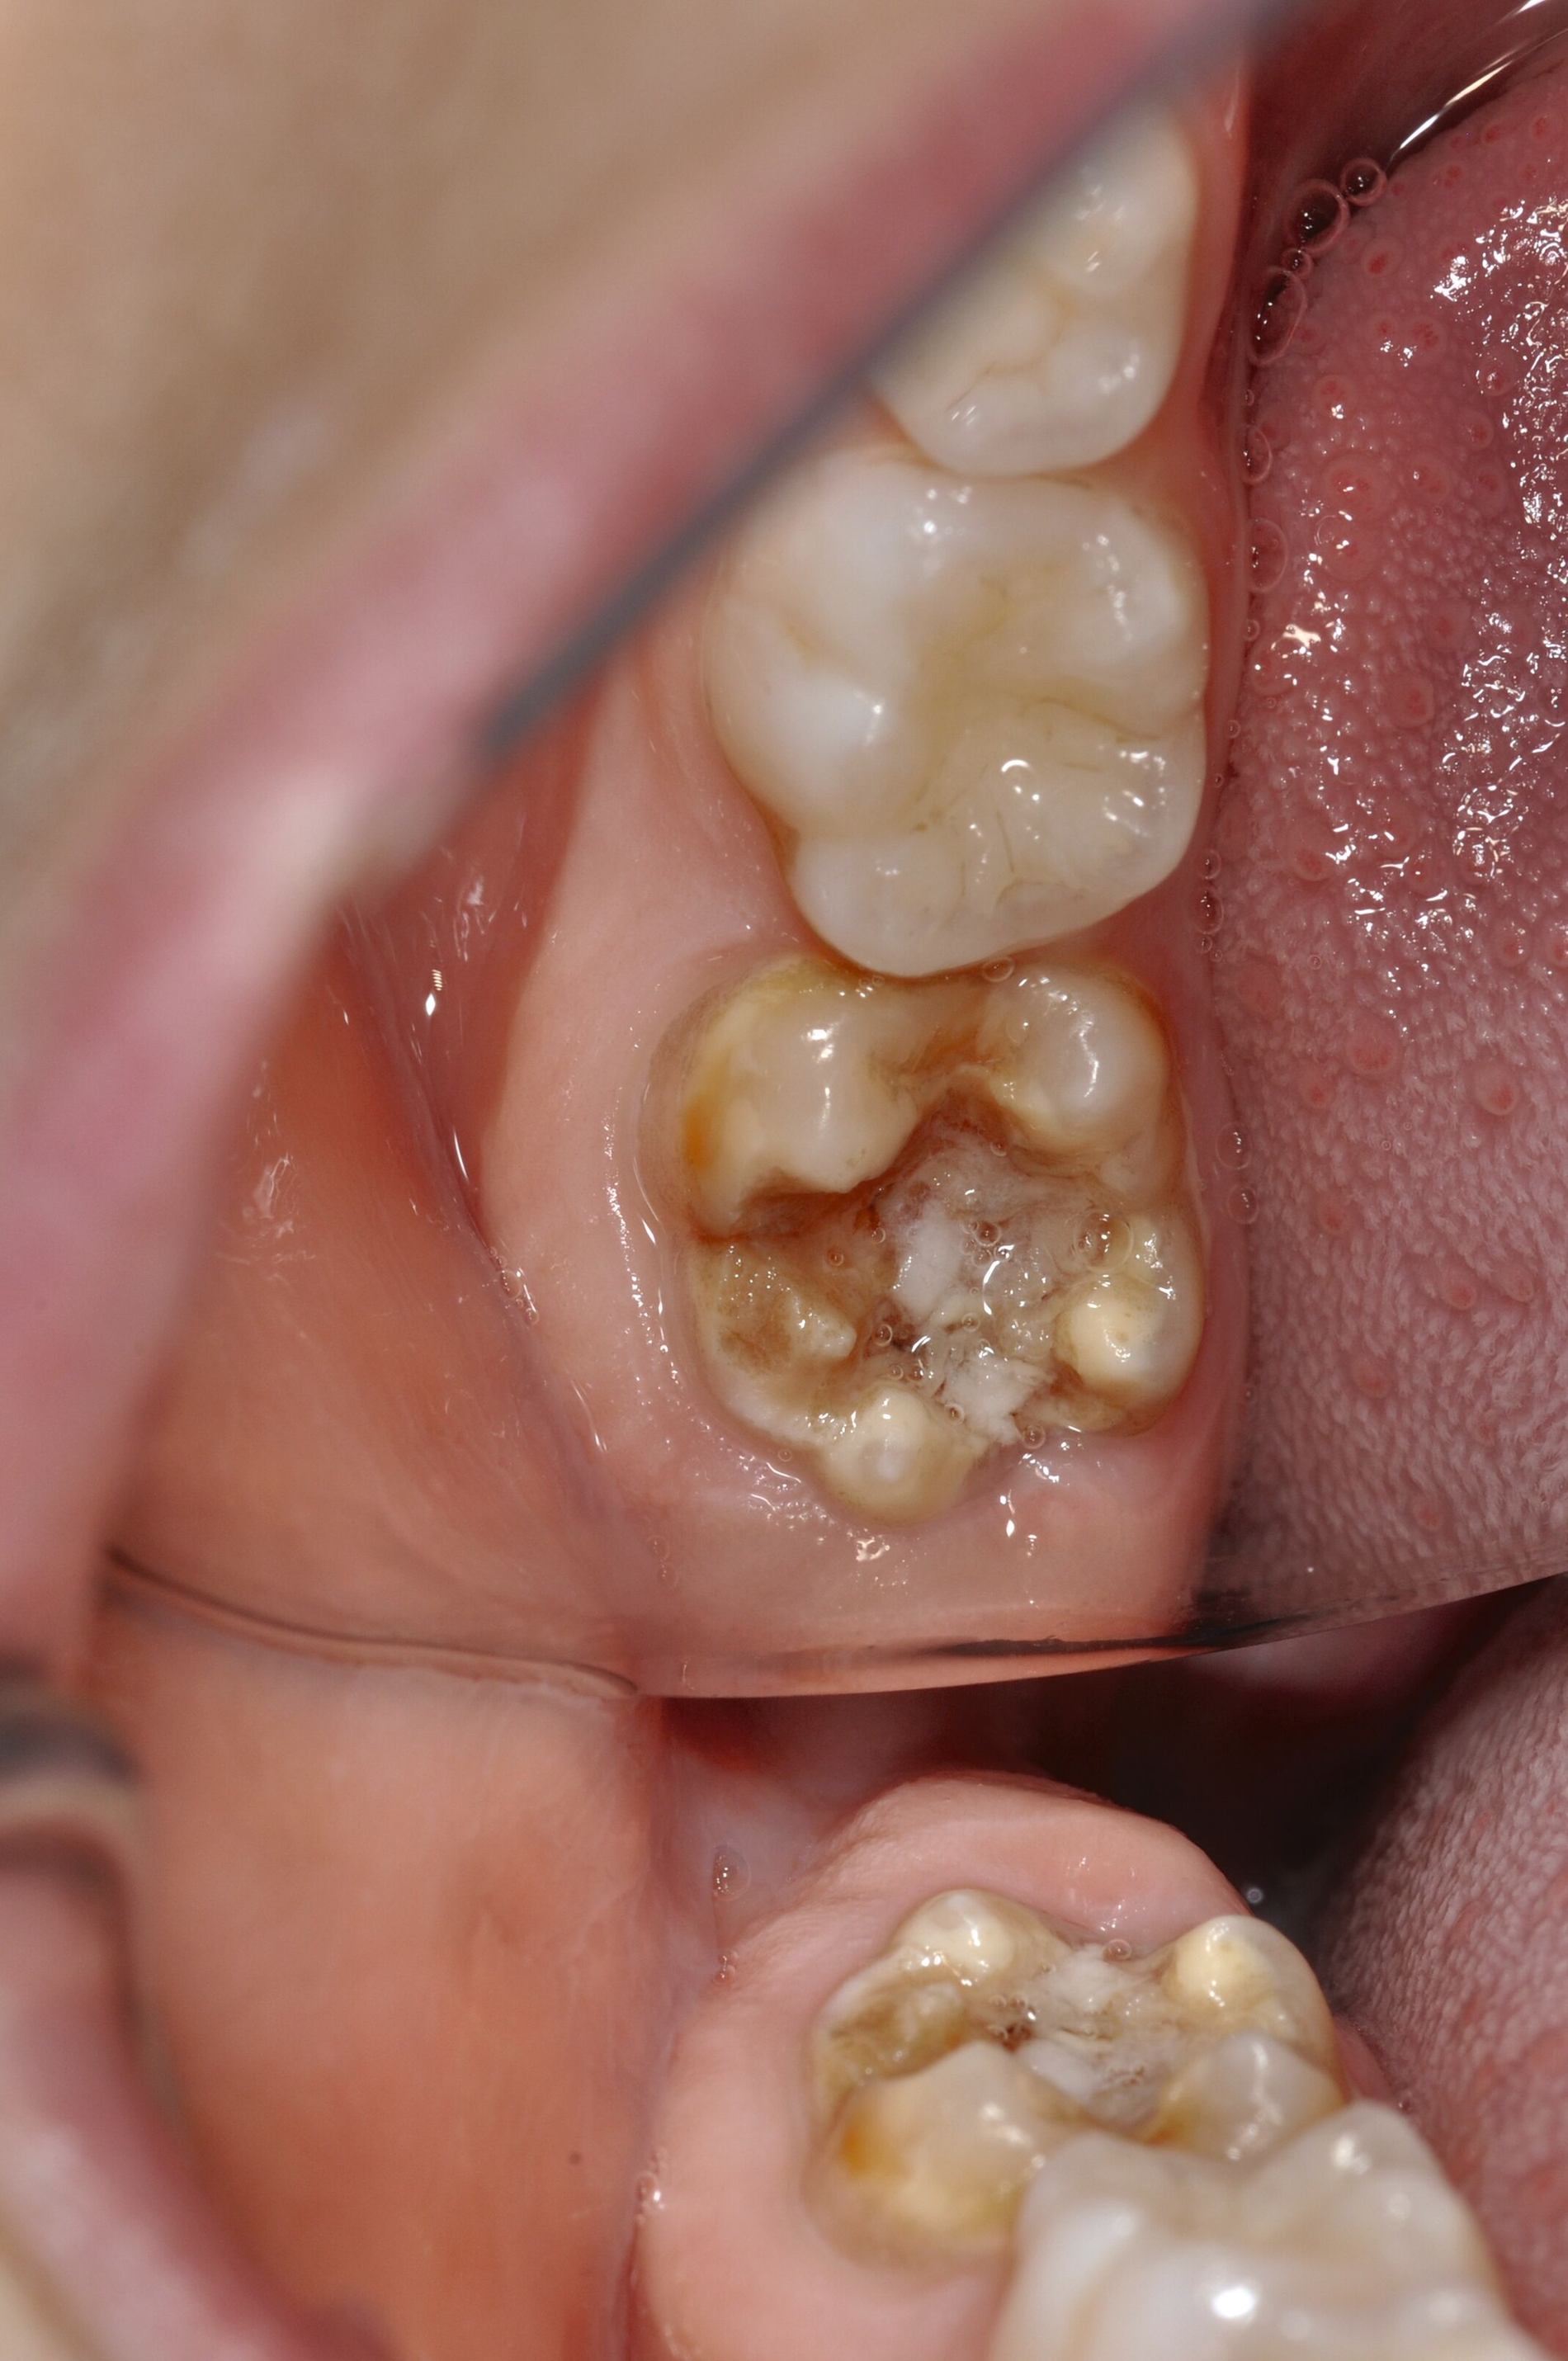

Diese Klassifikation dient als Grundlage für die Therapieempfehlungen. Deutlich wird, dass aufgrund der Symptomatik die Therapie der Zähne höchst unterschiedlich ausfällt. Dass etwa eine Opazität ohne Überempfindlichkeit (Index 1, Abbildung 1) ein anderes therapeutisches Vorgehen erfordert als ein Zahn mit nahezu komplettem Einbruch der Zahnoberfläche und mit Hypersensitivität (Index 4, Abbildung 2), ist offensichtlich.

Die Therapie C hat das Ziel, MIH-Zähne vorübergehend zu versorgen, bis der vollständige Durchbruch der Zähne eine adhäsive Restauration ermöglicht, um die hypersensiblen Zähne zu desensibilisieren oder/und die Mitarbeit für die weitere Behandlung aufzubauen. Vor dem Hintergrund des erhöhten Kariesrisikos dieser Zähne (Abbildung 2) muss durch die Maßnahmen eine Kariesprogression vermieden werden.

Als mögliche Maßnahme steht eine Abdeckung der Defekte mittels konventioneller Glasionomerzemente (GIZ) zur Verfügung. Vorteil der Materialien ist die schnelle und einfache Applikation der Zemente. Bei MIH-Molaren werden diese in der Regel mittels der sogenannten ART-Technik (Atraumatic Restorative Treatment) eingesetzt [Grossi et al., 2018]. Dabei wird lediglich mit einem Handinstrument die Zahnoberfläche gereinigt und gegebenenfalls Karies exkaviert. Anschließend wird die Kavität unter relativer Trockenlegung mit dem GIZ aufgefüllt.

Der Vorteil der Methode ist, dass die betroffenen Zähne auch ohne Lokalanästhesie und Präparation versorgt werden können. Die temporäre Versorgung ermöglicht es, die Patienten an die zahnärztliche Behandlung zu gewöhnen. Häufig führt diese temporäre Versorgung auch zu einer Reduktion der Hypersensitivität der MIH-Zähne. Nachteil der GIZ-Versorgung ist das Risiko einer Füllungsfraktur oder eines vollständigen Verlusts der Füllung (Abbildung 4). Aktuelle Erhebungen bestätigen eine Erfolgsrate von über 80 Prozent nach einem bis zwei Jahren [Durmus et al., 2021; Mahfouz et al., 2025].

Der Behandlungsfall (Abbildung 4d) veranschaulicht die Schwächen des Verfahrens. Wird das Angebot der regelmäßigen Kontrollen nicht wahrgenommen, so droht bei Verlust der Füllung die Kariesprogression. In dem vorliegenden Fall konnte jedoch eine endodontische Maßnahme vermieden und durch die selektive Kariesentfernung die Zahnhartsubstanz weitestgehend erhalten werden.